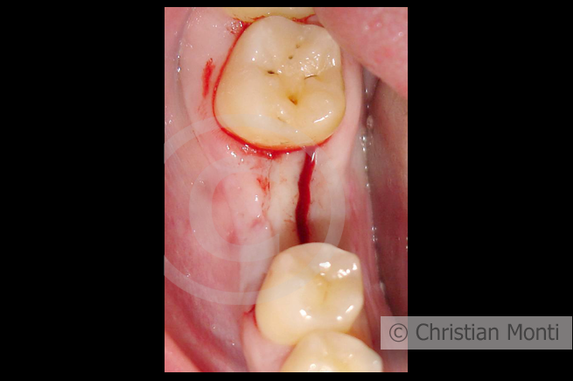

EDENTULIA SINGOLA

Impianto dilazionato in sostituzione di un molare inferiore